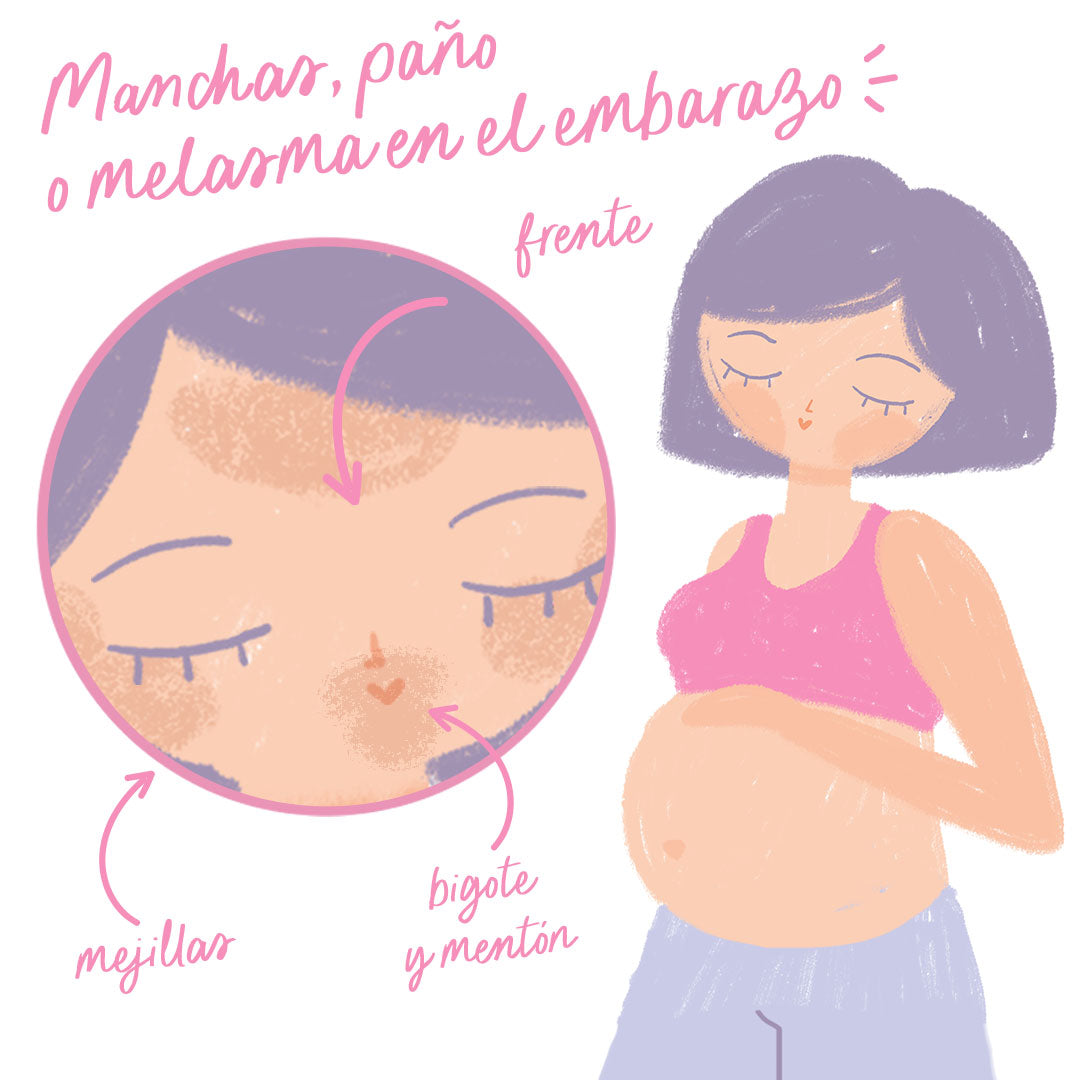

Es muy frecuente que a las mujeres les aparezcan manchas en la cara durante su embarazo. A estas manchas comúnmente se les conoce como melasma en la cara, cloasma, “mascara del embarazo” y comúnmente paño en la cara. No son las típicas manchas por la exposición solar, el melasma es simétrico y bilateral, lo que significa que sale la misma mancha en los 2 lados de la cara. Generalmente en mentón, mejillas, zona del “bigote”, frente y nariz. El paño puede aparecer a partir del 2º mes del embarazo.